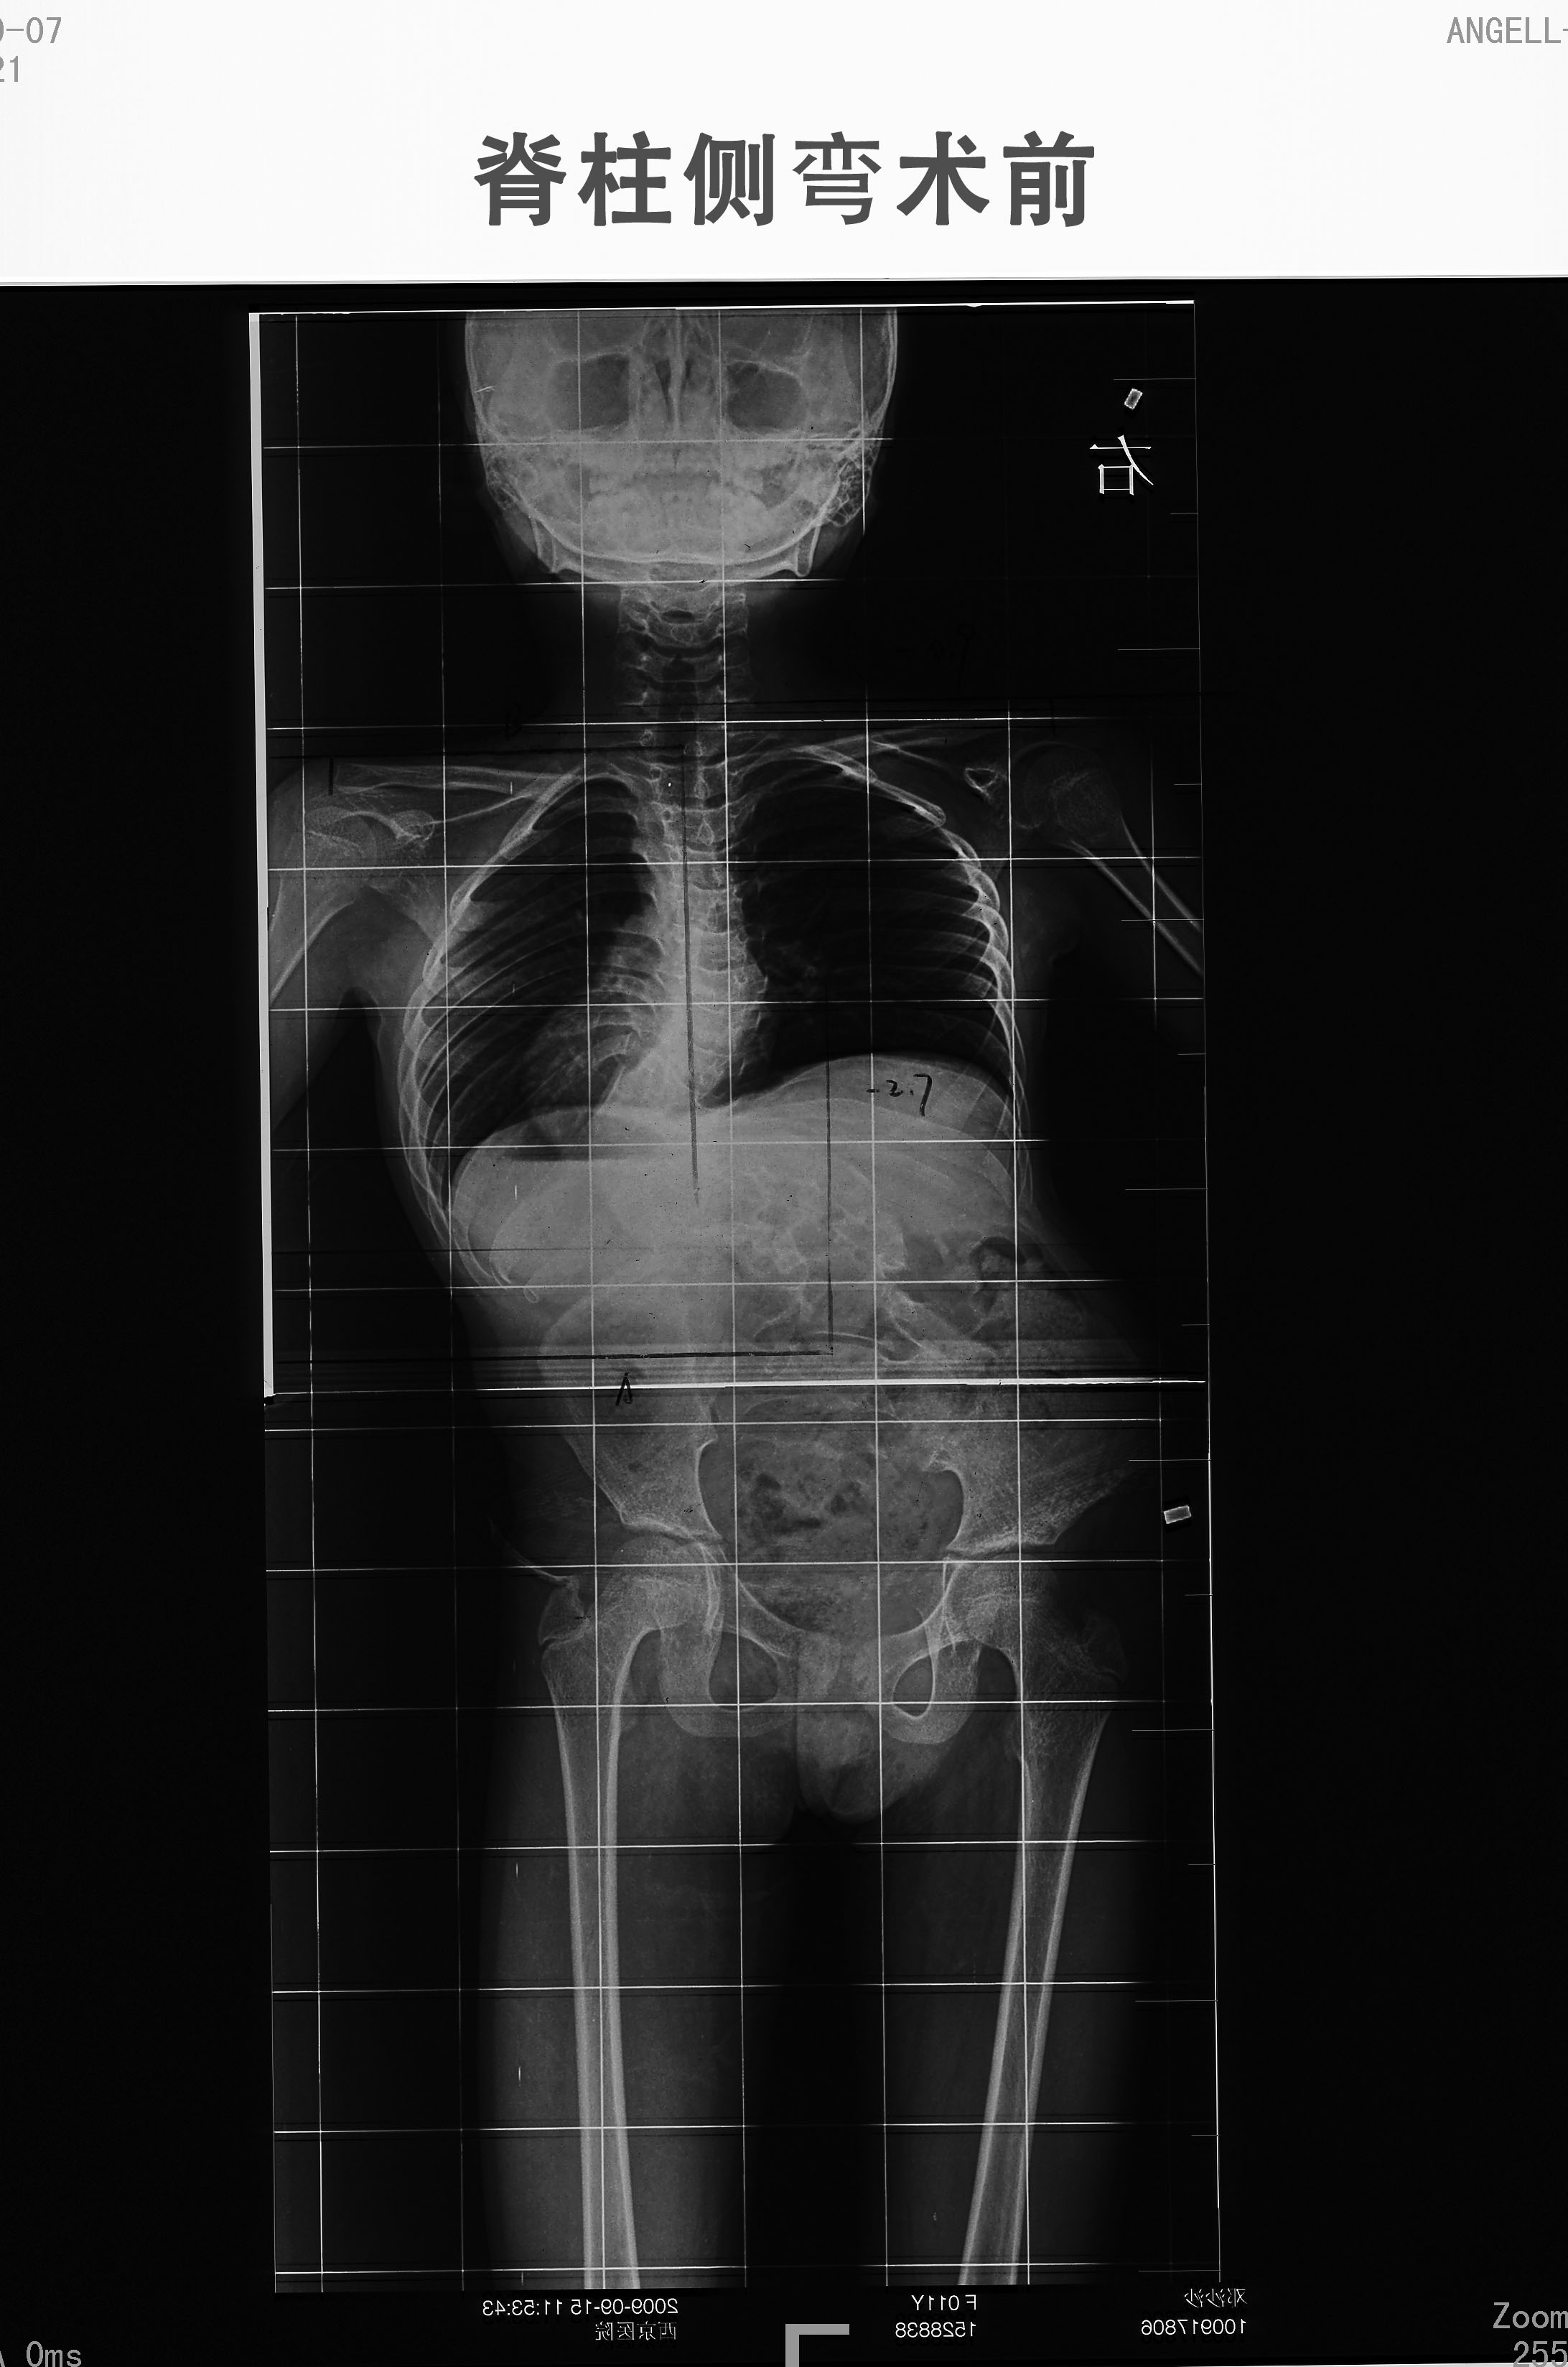

脊柱側(cè)彎治療案例(二十一)

癥狀和診斷:由于這兩種類型的脊柱側(cè)彎都與關(guān)節(jié)炎有關(guān),因此許多病人都會有背痛和肌肉疲勞,也有可能會腿疼。較大的側(cè)彎(超過40度)因側(cè)彎大小的增加應定期檢查。脊柱側(cè)彎和/或骨質(zhì)疏松癥的惡化會導致高度的降低連同其他癥狀如前所述。評估涉及普通X射線、核磁共振掃描的使用和可能使用CT掃描。這些研究有助于鑒別脊椎和周圍的神經(jīng)根和可能與脊柱畸形有關(guān)的脊髓的的異常。